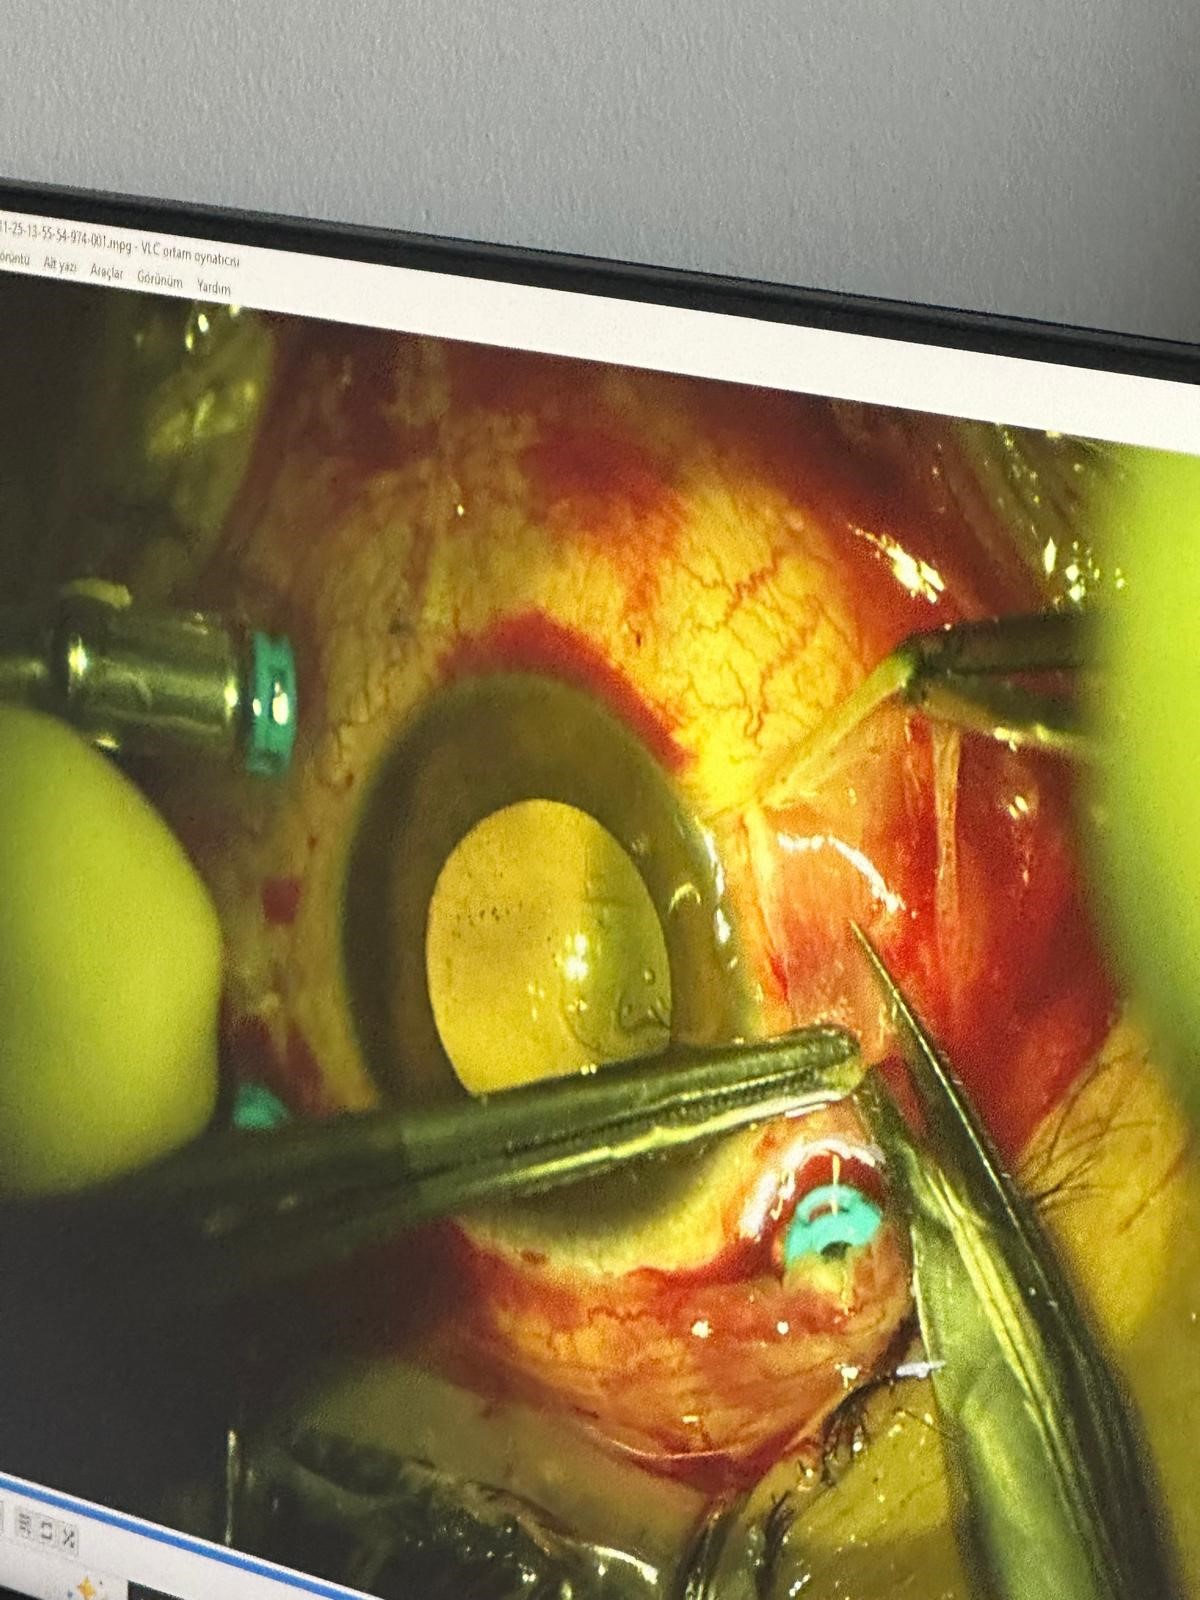

İhbar üzerine olay yerine polis ve sağlık ekipleri sevk edildi. Sağlık ekipleri; damadın saçmalar nedeniyle gözünden, başından ve kulağından yaralandığını tespit etti. İlk müdahalenin ardından Nevşehir Devlet Hastanesi'ne kaldırılan Mert G., daha sonra ileri tedavi için Kayseri Erciyes Üniversitesi Tıp Fakültesi Hastanesi'ne sevk edildi.

Şu ana kadar dört operasyon geçirmesine rağmen görmesinde bir iyileşme sağlanamadı. Göz nakli gerekebilir. Araçta yaklaşık 20 saçma izi var. Müvekkilimin gözünde, kulağında ve başında saçmalar bulunuyor."